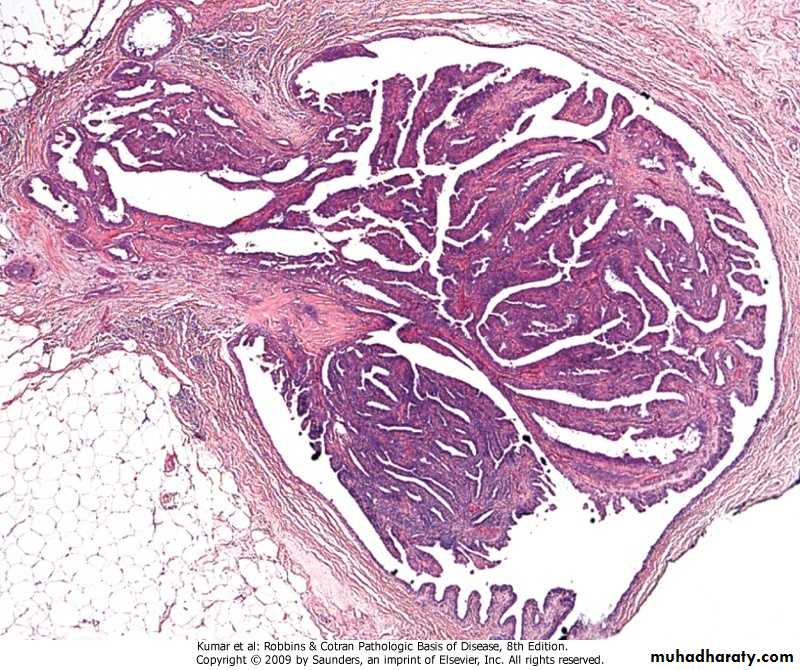

Leiomyoma

.in epithelial neoplasms nomenclature

depends on• -cell of origin, (adenoma)

• -microscopic pattern &/or macroscopic

• architecture (adenoma, papilloma,

• cystadenoma, papillary cystadenoma)